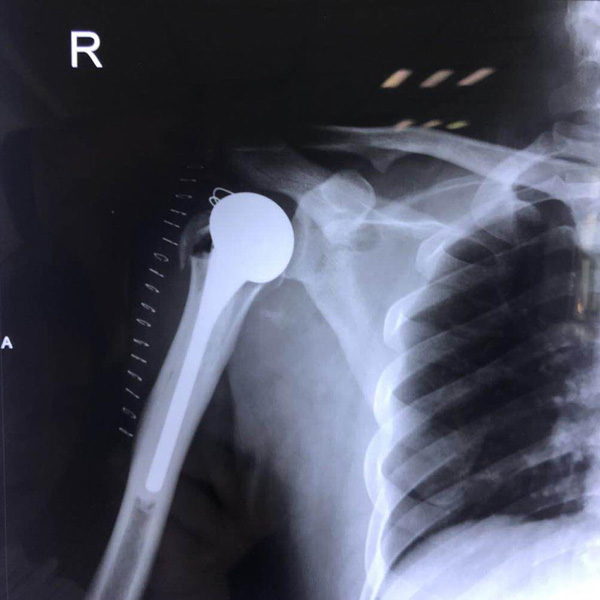

右側肱骨頭置換

患者郭某,男,40歲,因嚴重車禍導致“右肱骨頭粉碎性骨折”,一般的手術很難將粉碎的骨折塊拼接起來,即便大致的拼接起來,因為骨面的不平......